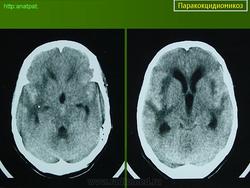

ГМ. Паракокцидиомикоз. +

Паракокцидиомикоз.

Множественные "узловые образования" имитирующие метастазы.